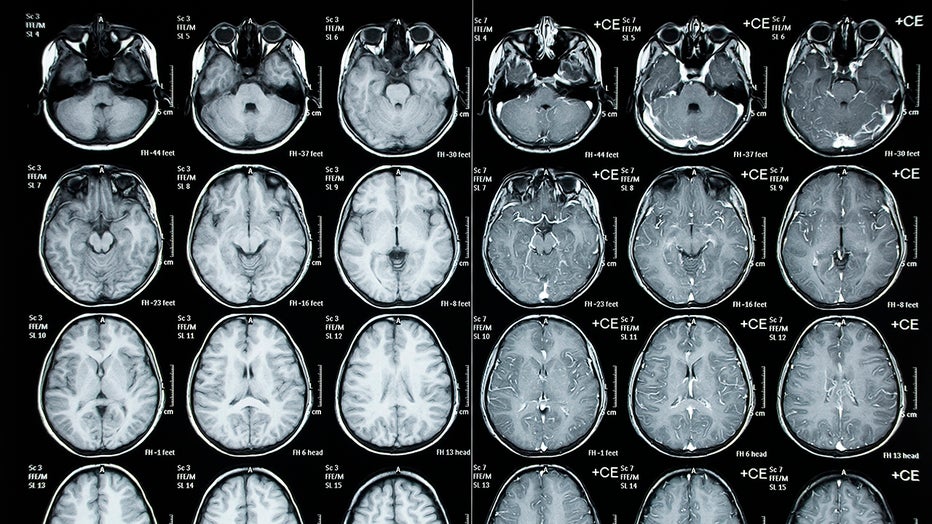

Child brain scans (Getty Images)